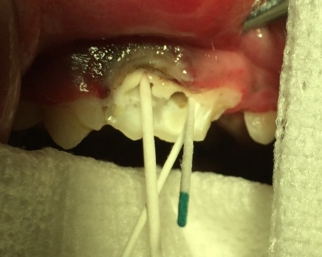

ヒトのような虫歯は大変少なく、通常は玩具による破折により生じた虫歯が大半をしめます。破折後8時間で「虫歯」となるために、できるかぎり早く病院へ行くことが大切です。遠方の方ではまずはお近くで抗生物質を処方していただくとよいでしょう。ヒトで歯医者にかかると、なにか口のなかをガリガリと削られ、そのあとに苦い薬をつけられて、1週間後に来院というイメージがあると思います。当日は、お口の中をみると虫歯の部位は、「白いかぶせ物」がしてあると思います。1週間後に再度、歯医者にかかると、そのかぶせ物をとられ、一部をインレーとよばれる「銀色の詰め物」をされると思います。ペットでも治療はなんら変わりません。異なる点といえば、虫歯の治療には必ず全身麻酔が必要になるという事です。簡単な虫歯であれば、ヒトと同様、虫歯部位を削り取り、詰め物をします。虫歯が深ければやはり神経を抜く(抜髄)という処置になります。当院では、クラウンダウン法という方法を用いておりますが、初回のアクセスを電動の低トルクエンジンで、その後は時と場合によりますが、ハンドファイルにてアクセスおよび治療していきます。ペットにもっとも生じるP4破折においては、3アクセスポイントがありますが、2つは非常にわかりやすいのですが、小型犬では3つ目のアクセスポイントが非常に難解なことがあります。アクセスポイントは光重合レジンで被覆し終了いたします。

青:アクセスポイント 緑:破折部位

青:根管のアクセスポイント

各々の根管にファイルを挿入し根管長を測定

ペーパーポイントにて根管を乾燥

ポータブルレントゲンによる術中写真